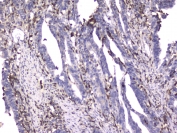

IHC testing of FFPE human rectal cancer with ITGB2 antibody at 2ug/ml. HIER: boil tissue sections in pH6, 10mM citrate buffer, for 10-20 min followed by cooling at RT for 20 min.